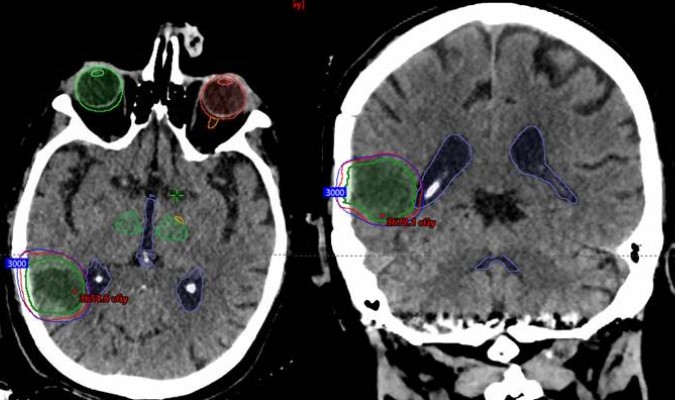

SRS planning images (merged CT & MRI) in the axial (left), coronal (middle) and, sagittal (right) planes with overlapping radiation dosing information. Note the conformity of the Stereotactic Radio Surgery (SRS) dose (demonstrated by the concentric rings around the tumor resection cavity) that treat the tumor bed without exposing the remainder of the brain to high doses of radiation.